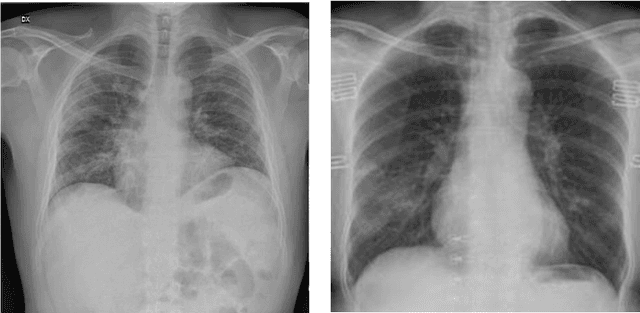

Abstract:The new coronavirus disease (COVID-19) has been declared a pandemic since March 2020 by the World Health Organization. It consists of an emerging viral infection with respiratory tropism that could develop atypical pneumonia. Experts emphasize the importance of early detection of those who have the COVID-19 virus. In this way, patients will be isolated from other people and the spread of the virus can be prevented. For this reason, it has become an area of interest to develop early diagnosis and detection methods to ensure a rapid treatment process and prevent the virus from spreading. Since the standard testing system is time-consuming and not available for everyone, alternative early-screening techniques have become an urgent need. In this study, the approaches used in the detection of COVID-19 based on deep learning (DL) algorithms, which have been popular in recent years, have been comprehensively discussed. The advantages and disadvantages of different approaches used in literature are examined in detail. The Computed Tomography of the chest and X-ray images give a rich representation of the patient's lung that is less time-consuming and allows an efficient viral pneumonia detection using the DL algorithms. The first step is the pre-processing of these images to remove noise. Next, deep features are extracted using multiple types of deep models (pre-trained models, generative models, generic neural networks, etc). Finally, the classification is performed using the obtained features to decide whether the patient is infected by coronavirus or it is another lung disease. In this study, we also give a brief review of the latest applications of cough analysis to early screen the COVID-19, and human mobility estimation to limit its spread.

Abstract:The new coronavirus 2019, also known as COVID19, is a very serious epidemic that has killed thousands or even millions of people since December 2019. It was defined as a pandemic by the world health organization in March 2020. It is stated that this virus is usually transmitted by droplets caused by sneezing or coughing, or by touching infected surfaces. The presence of the virus is detected by real-time reverse transcriptase polymerase chain reaction (rRT-PCR) tests with the help of a swab taken from the nose or throat. In addition, X-ray and CT imaging methods are also used to support this method. Since it is known that the accuracy sensitivity in rRT-PCR test is low, auxiliary diagnostic methods have a very important place. Computer-aided diagnosis and detection systems are developed especially with the help of X-ray and CT images. Studies on the detection of COVID19 in the literature are increasing day by day. In this study, the effect of different batch size (BH=3, 10, 20, 30, 40, and 50) parameter values on their performance in detecting COVID19 and other classes was investigated using data belonging to 4 different (Viral Pneumonia, COVID19, Normal, Bacterial Pneumonia) classes. The study was carried out using a pre-trained ResNet50 convolutional neural network. According to the obtained results, they performed closely on the training and test data. However, it was observed that the steady state in the test data was delayed as the batch size value increased. The highest COVID19 detection was 95.17% for BH = 3, while the overall accuracy value was 97.97% with BH = 20. According to the findings, it can be said that the batch size value does not affect the overall performance significantly, but the increase in the batch size value delays obtaining stable results.

Abstract:Covid-19 is a very serious deadly disease that has been announced as a pandemic by the world health organization (WHO). The whole world is working with all its might to end Covid-19 pandemic, which puts countries in serious health and economic problems, as soon as possible. The most important of these is to correctly identify those who get the Covid-19. Methods and approaches to support the reverse transcription polymerase chain reaction (RT-PCR) test have begun to take place in the literature. In this study, chest X-ray images, which can be accessed easily and quickly, were used because the covid-19 attacked the respiratory systems. Classification performances with support vector machines have been obtained by using the features extracted with residual networks (ResNet-50), one of the convolutional neural network models, from these images. While Covid-19 detection is obtained with support vector machines (SVM)-quadratic with the highest sensitivity value of 96.35% with the 5-fold cross-validation method, the highest overall performance value has been detected with both SVM-quadratic and SVM-cubic above 99%. According to these high results, it is thought that this method, which has been studied, will help radiology specialists and reduce the rate of false detection.

Abstract:The 2019 novel coronavirus (COVID-19), with a starting point in China, has spread rapidly among people living in other countries, and is approaching approximately 305,275 cases worldwide according to the statistics of European Centre for Disease Prevention and Control. There are a limited number of COVID-19 test kits available in hospitals due to the increasing cases daily. Therefore, it is necessary to implement an automatic detection system as a quick alternative diagnosis option to prevent COVID-19 spreading among people. In this study, three different convolutional neural network based models (ResNet50, InceptionV3 and Inception-ResNetV2) have been proposed for the detection of coronavirus pneumonia infected patient using chest X-ray radiographs. ROC analyses and confusion matrices by these three models are given and analyzed using 5-fold cross validation. Considering the performance results obtained, it is seen that the pre-trained ResNet50 model provides the highest classification performance with 98% accuracy among other two proposed models (97% accuracy for InceptionV3 and 87% accuracy for Inception-ResNetV2).